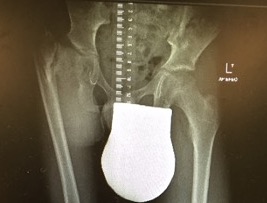

Aitken's Classification

Class A

- short femoral shaft with coxa vara

- head of femur present, neck may be absent early

- adequate acetabulum

- bony connection between head & neck present at maturity

- may be pseudarthrosis at point of connection